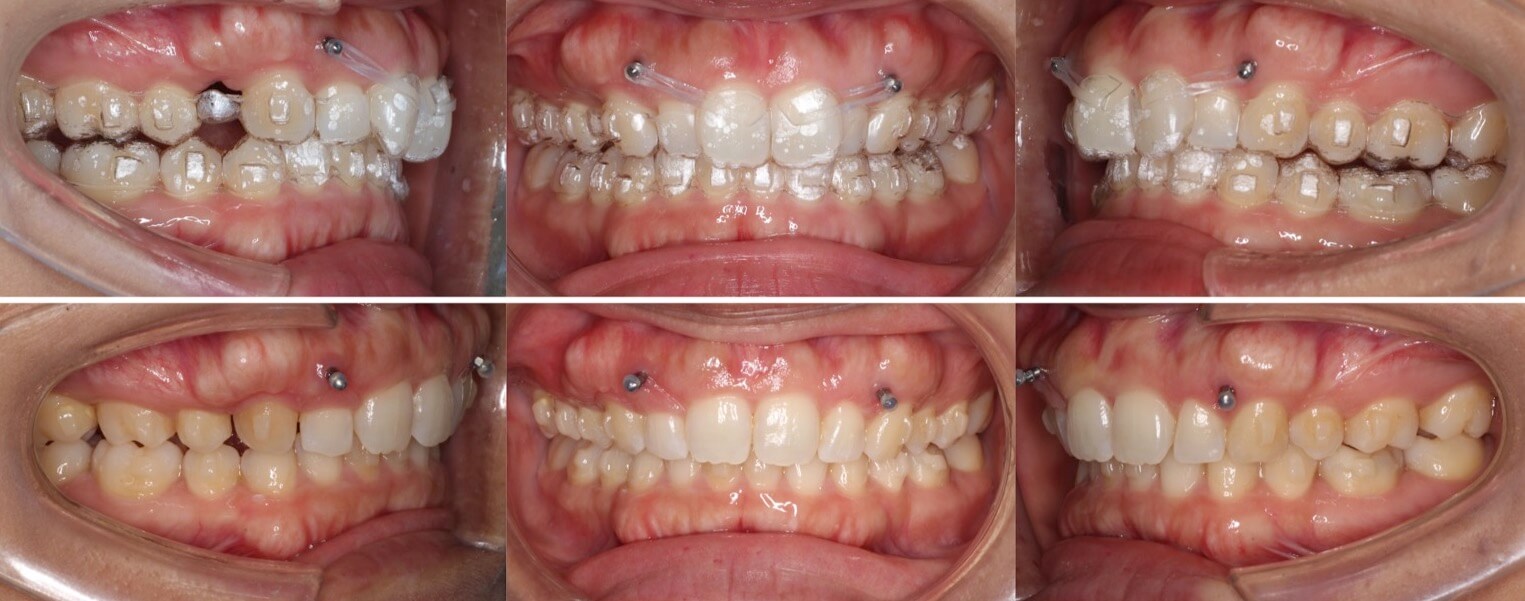

大学生男性・唇側矯正装置・4本抜歯

口元の突出もある重度の過蓋咬合症例は、表側矯正装置の方が確実に治療が可能です。このようなケースの治療期間は3年を超えてしまいます。側方のシザースバイトも併発しているため、下の歯並びにブラケット装置を装着する面積を確保する事に苦戦しました。治療途中は何回もワイヤーが上の歯で噛み切ってしまい折れてしまうため、複雑なワイヤーを併用する事で過蓋咬合を改善しました。

<症例概要>

主訴:口元の突出

年齢・性別:大学生男性

住まい:千葉県八千代市

症状:過蓋咬合・上下顎前突・左側シザースバイト

治療方針:抜歯空隙の閉鎖(最大固定)

治療装置:唇側矯正装置

固定装置:歯科矯正用アンカースクリュー(上頬側x2)

抜歯:上下左右4番(計4本)

治療期間:3年2か月

リテーナー:下フィックスタイプ+上下プレートタイプ

治療費用:968,000(税込)

代表的副作用:痛み・治療後の後戻り・歯根吸収・歯髄壊死・歯肉退縮

▶︎その他の副作用